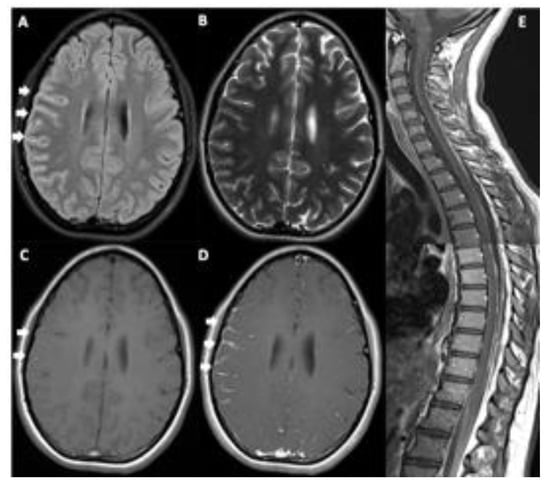

A 14-year-old girl presented to our hospital with headache, vomiting, and unilateral VI nerve palsy. The magnetic resonance imaging (MRI) detected a diffuse leptomeningeal enhancement of the right frontal lobe and spine (Figure 1). Cytological examination of the cerebrospinal fluid (CSF) showed the presence of neoplastic cells with abundant pigmented cytoplasm, large vesicular nuclei, and prominent nucleoli suspected to be melanoma cells (Figure 2 and Figure 3). The immunocytochemical positivity for HMB45 and Mart1 confirmed the hypothesis. A right frontal craniotomy with en-bloc cerebral and leptomeningeal biopsy confirmed melanomatosis. The NRASQ61K mutation was detected by Sanger sequencing performed on DNA extracted from both tumor sample and CSF neoplastic cells. NRASQ61K is a hotspot mutation located in the GTP-binding region of the NRAS protein, conferring a loss of function as indicated by activation of downstream pathway signaling, increased survival, and transformation of cultured cells (Figure 4). Specifically, activated mutant NRASQ61K has been demonstrated to drive aberrant melanocyte signaling, survival, and invasiveness via Rac1-dependent mechanism [3]. Both CSF and tumor biopsy cells shared similar pathology and molecular aspects. Extra CNS localization was excluded and a diagnosis of PLMM in the absence of a neurocutaneous melanosis (NCM) was made. The patient was treated with conventional chemotherapy based on temozolomide and intrathecal liposomal cytarabine. A concomitant treatment with everolimus was administered in order to block NRAS activation by m-TOR inhibitor cascade, followed by ipilimumab to induce cytotoxic lymphocytes activation and expansion, plus nivolumab to inhibit PDL1. The disease was under control for six months, followed by rapid progression and death.

Figure 1. Brain MRI ((AD), axial images) and spine ((E), sagittal Gd T1w image). Brain MRI shows diffuse leptomeningeal hyperintensity in the FLAIR image (arrows, (A)), not appreciable in the T2w image (B), with discontinuous mild spontaneous T1w hyperintensity (arrows, (C)) and diffuse leptomeningeal contrast-enhancement (Gd T1w, arrows, (D)). It is also appreciable diffuse spinal leptomeningeal contrast-enhancement (E).